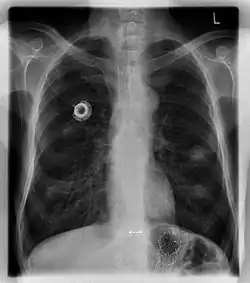

Une chambre à cathéter implantable ou cathéter à chambre implantable (CCI), aussi appelée chambre implantable percutanée (CIP), ou PAC d'après la marque Port-a-Cath, est un dispositif médical permettant une voie veineuse centrale permanente pour les traitements injectables ambulatoires à longue durée comme la chimiothérapie.

La chambre est palpable sous la peau près de la clavicule droite et est prolongée d'un tube appelé cathéter d'une vingtaine de centimètres depuis la veine jugulaire interne ou la veine sous-clavière jusqu'à la veine cave supérieure.